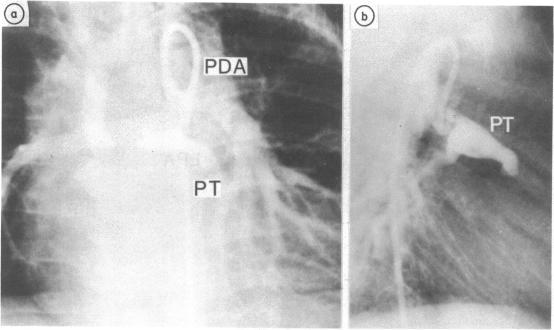

Juxtaductal left pulmonary artery obstruction in pulmonary atresia.

The morphology of the central pulmonary artery was studied by selective angiography in 21 previously unoperated patients (aged 11 days-21 years, median 4 years) with pulmonary atresia associated with various types of congenital heart disease. Angiographic findings were confirmed at operation in 10 patients. There was juxtaductal obstruction of the left pulmonary artery in two thirds of the patients with complete atresia in a quarter. Six of seven patients without juxtaductal obstruction had pulmonary valve atresia, but all nine patients with juxtaductal stenosis had truncal atresia. No patient had stenosis of the right pulmonary artery.